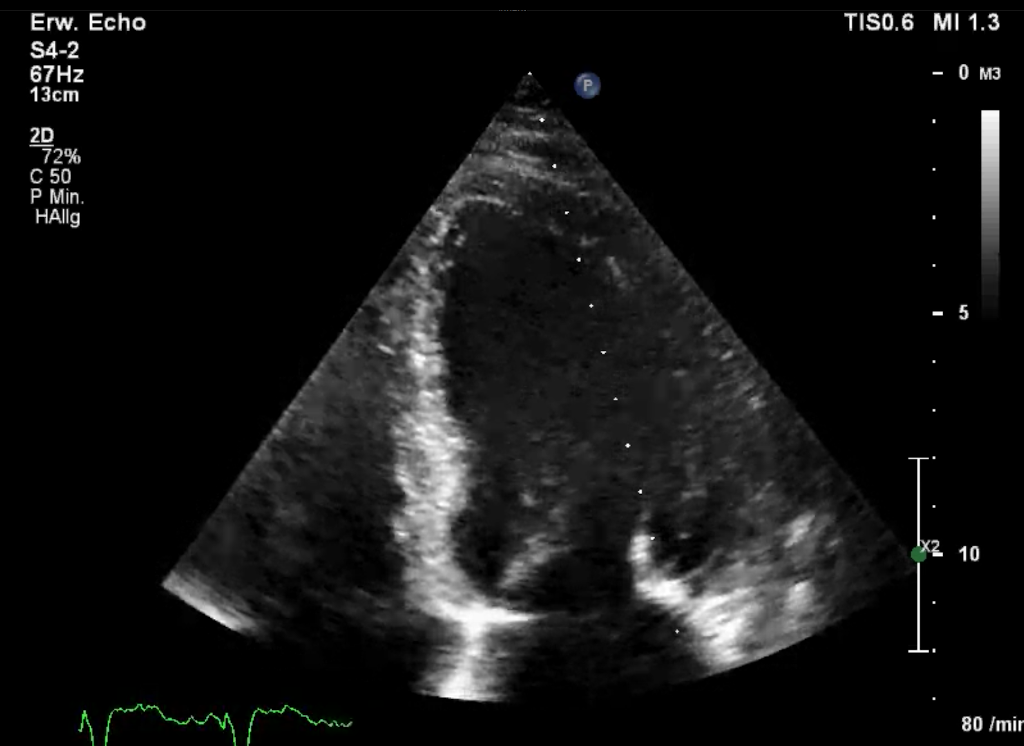

B-Mode (brightness modulation)

In der Darstellung des empfangenen Echo wird die Echostärke im Gegensatz zum A-Mode nicht mehr auf der y-Achse aufgetragen sondern in Helligkeit dargestellt

• Wird der Ultraschall-Meßstrahl an einer Stelle belassen und das empfangene Signal auf einer Zeitachse abgebildet lassen sich Bewegungen der Strukturen darstellen (= M-Mode)

• Wird der Ultraschall-Meßstrahl (automatisch) geschwenkt lässt sich mittels B-Mode hingegen ein zweidimensionales Bild aufbauen (= 2D-Bild)

2D-Bild

2D-Bild (realtime)